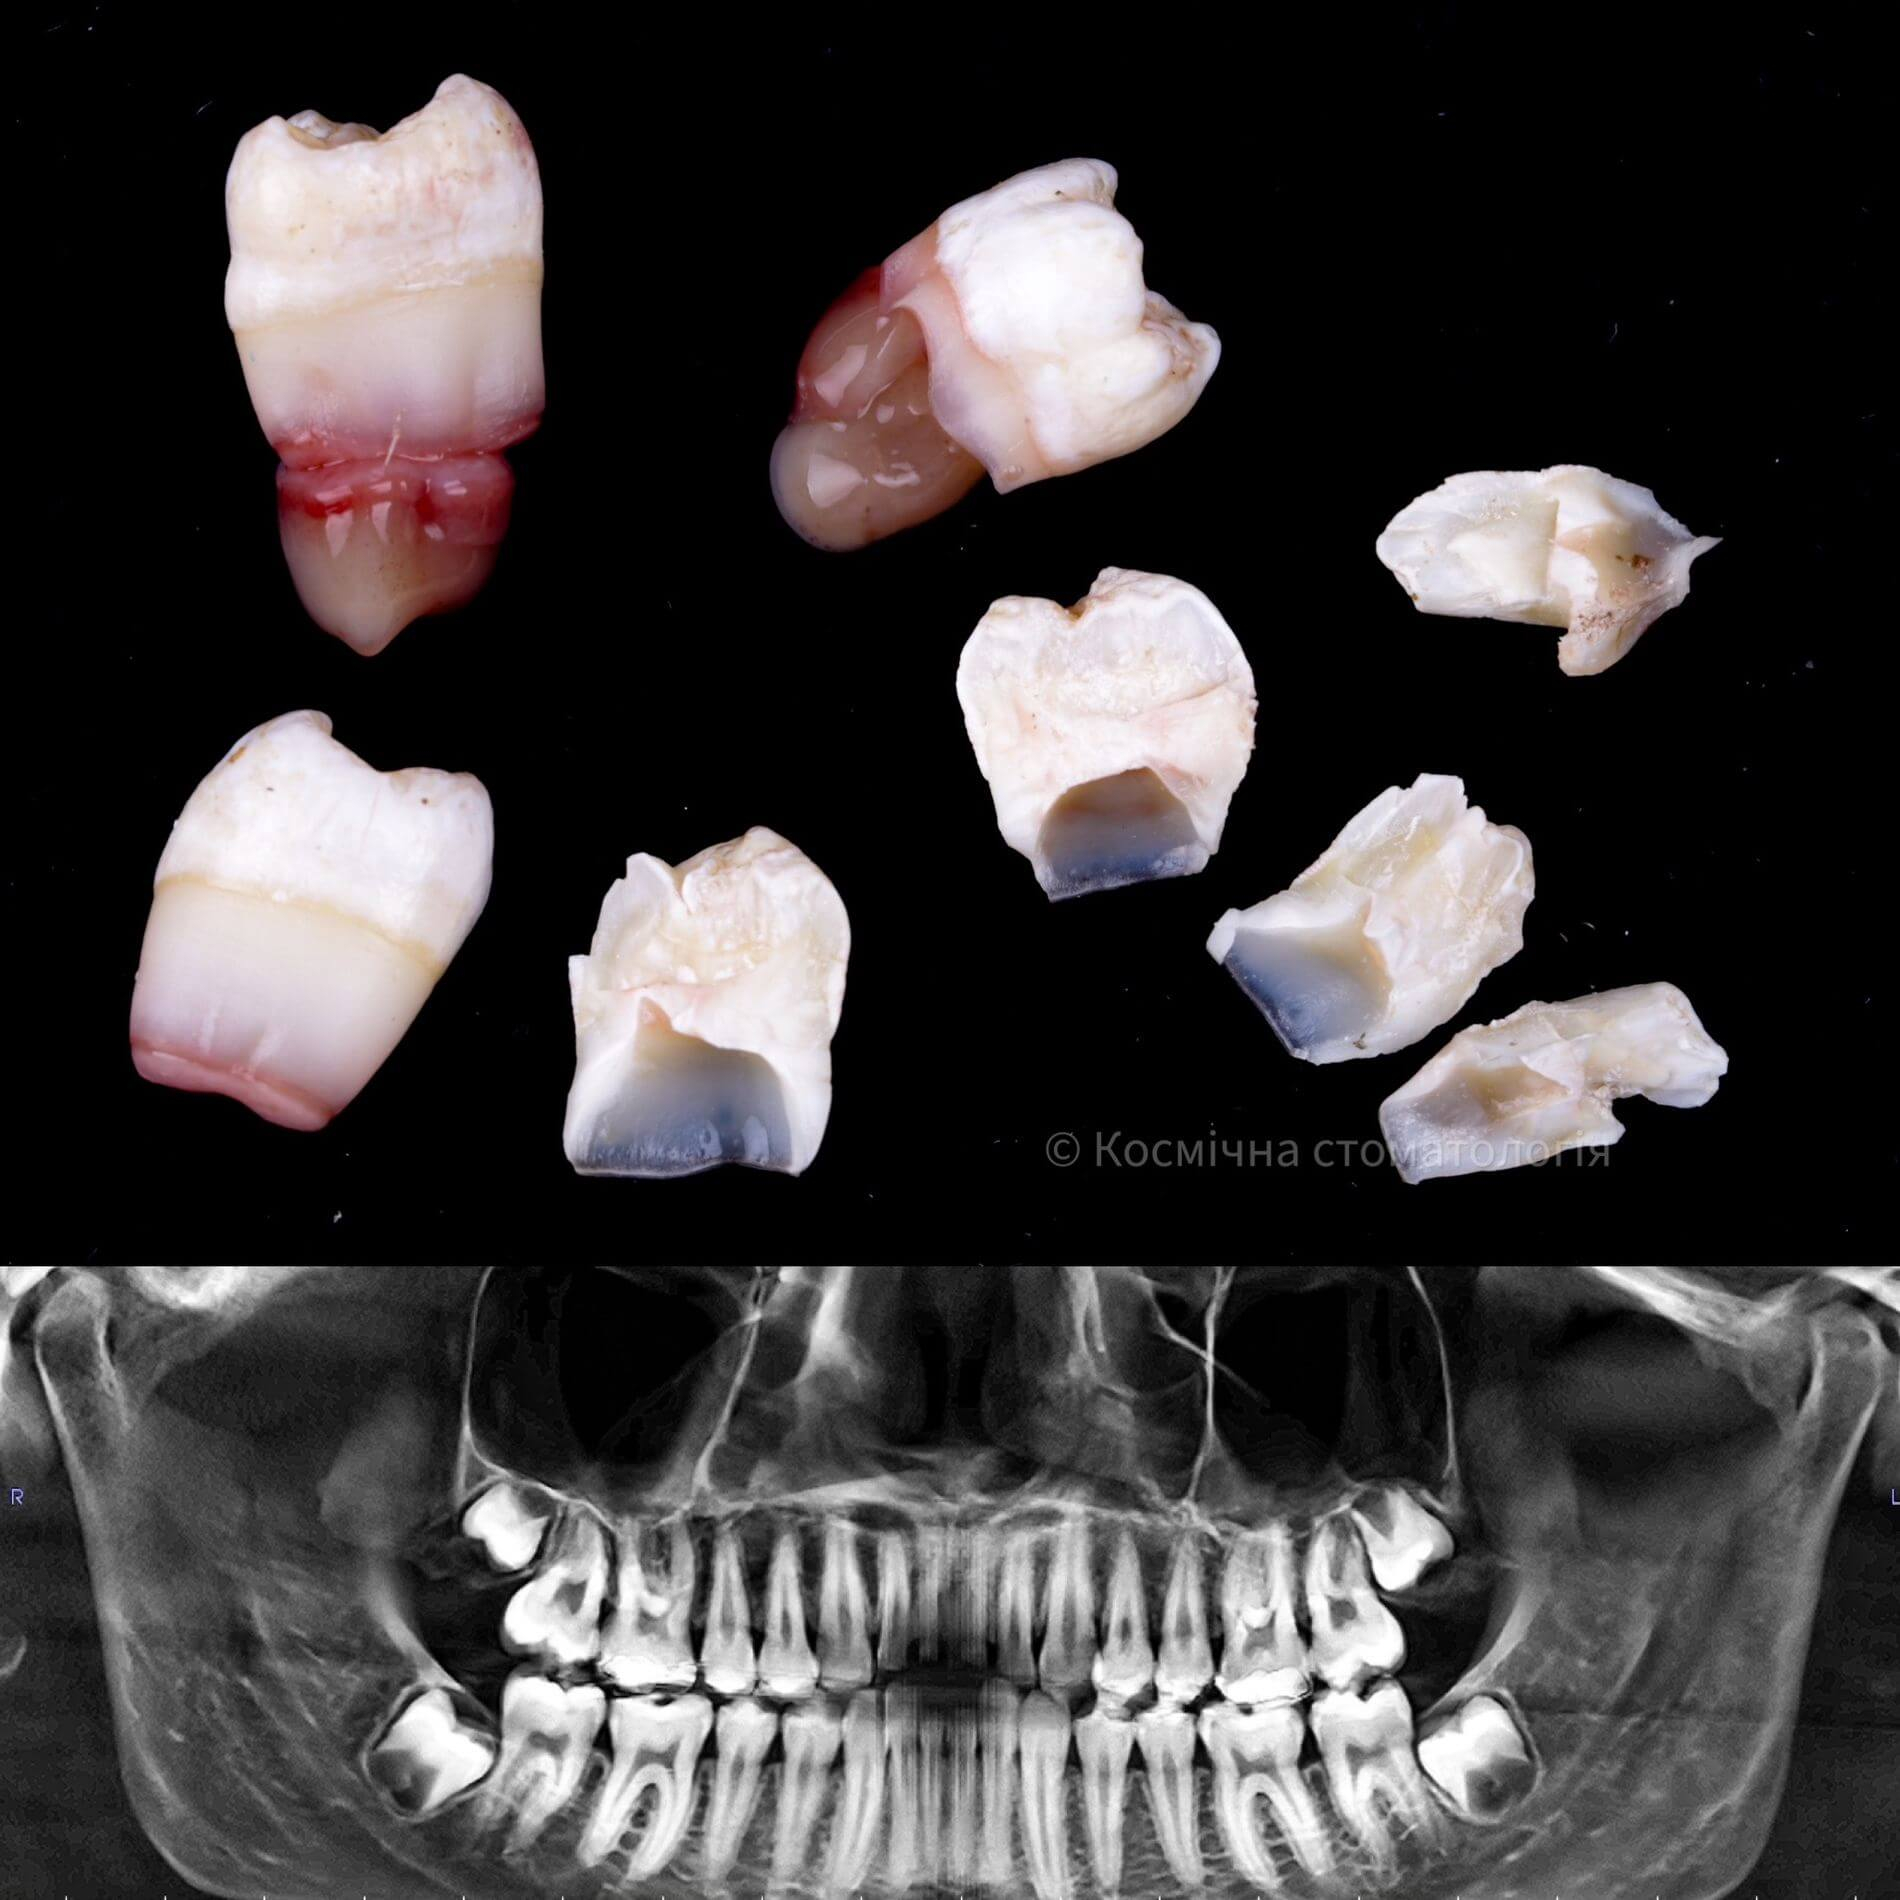

Види видалення зубів мудрості

- Повне видалення зуба - якщо зуб повністю прорізався та має зрощені корені.

- Окреме видалення коронки зуба та його коренів - якщо зуб прорізаний і корені ростуть по окремо.

- Видалення зуба за схемою 1 або 2 із розрізом ясна - якщо зуб прорізаний частково.

- Розріз ясна, звільнення зуба від прилеглої кістки ультразвуком та видалення за схемою 1 або 2 - якщо зуб не прорізався, але турбує.

Видаляти зуб мудрості рекомендується тоді, коли він давить на зубний ряд та посуває інші зуби, завдає болю або сам вже пошкоджений карієсом.

Вирвати зуб мудрості у Львові можна простіше, ніж тобі здається, в Космічній стоматології Драганчука. Почни цей шлях з простого кроку - первинної зустрічі з хірургом-стоматологом. На консультації ми зробимо основне – скеруємо тебе на 3D комп’ютерну томографію, щоб врахувати близькість нижньощелепного нерва (нижні 8-ки) та верхньощелепної пазухи (верхні 8-ки) та складемо план видалення зубів.